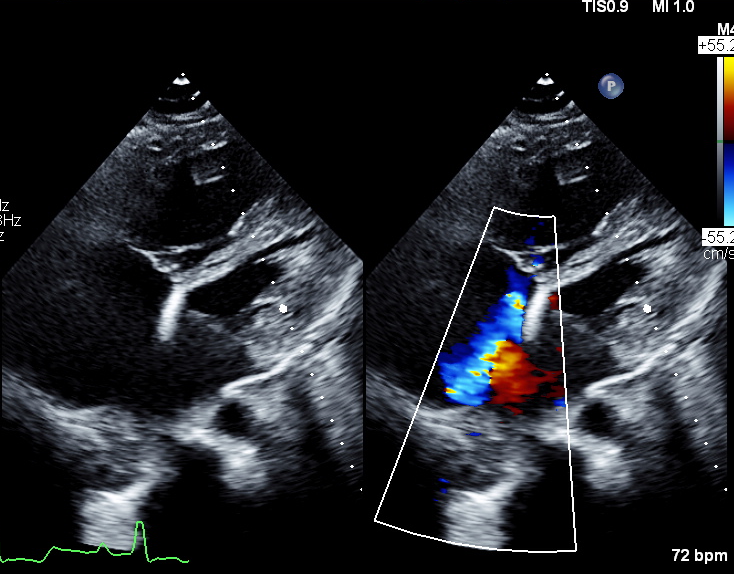

Secundum ASD with bidirectional shunt

Dilated RA and RV

-Vasoreactivity results may be skewed with O2-Severe tricuspid regurgitation due to prolapsed anterior leaflet and retracted septal leaflet

- Atrial septal defect secundum with pulmonary hypertension

This case highlights our patient with longstanding secundum ASD and pulmonary arterial hypertension who developed dynamic left main coronary compression by a dilated pulmonary artery, confirmed on IVUS (MLA 12.8¡æ6.7 mm©÷, minimal plaque). Cardiac MRI showed Qp:Qs 1.86 and right-sided dilatation; right-heart catheterization revealed elevated but partially reversible PVR (4.9¡æ3.8 WU with iNO). A multidisciplinary, safety-first ¡°treat-and-reassess¡± strategy (targeted PAH therapy with planned fenestrated ASD closure if PVR improves) avoided premature high-risk interventions and provides a practical framework for similar complex ACHD patients.